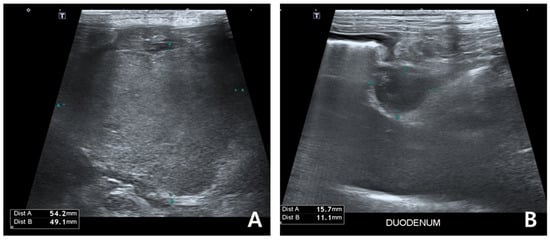

2. Case Description